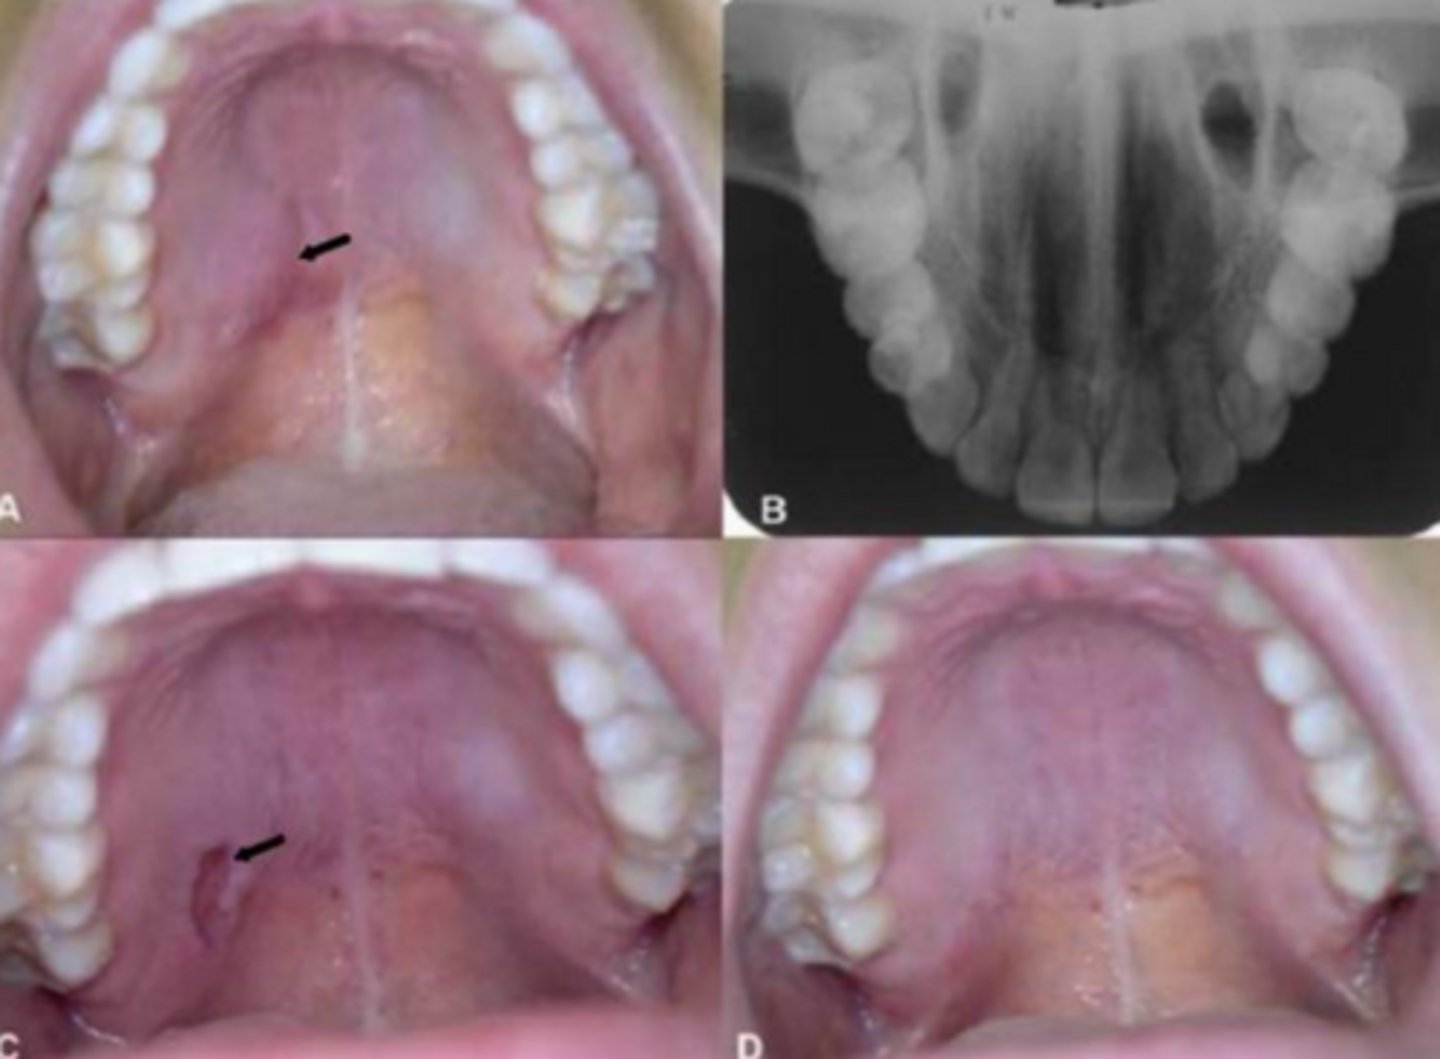

what reactive salivary gland lesion is a locally destructive inflammatory condition probably due to ischemia leading to infarction?

necrotizing sialometaplasia

what reactive salivary gland lesion mimics a malignant process (both clinically and microscopically) and mainly occurs on the posterior palate?

what reactive salivary gland lesion appears as a non-ulcerated swelling then a craterlike ulcer after 2-3 weeks, then finally resolves in 5-6 weeks?

what reactive salivary gland lesion is a local ischemia that causes the infarction of salivary glands leading to squamous metaplasia and hyperplasia of epithelium (resembling SCC)?

what reactive salivary gland lesion always requires biopsies to establish a diagnosis due to worrisome presentations and resolves on its own in 5-6 weeks spontaneously?